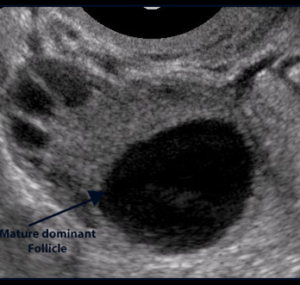

- Follicular Monitoring

- Ovulation Trigger